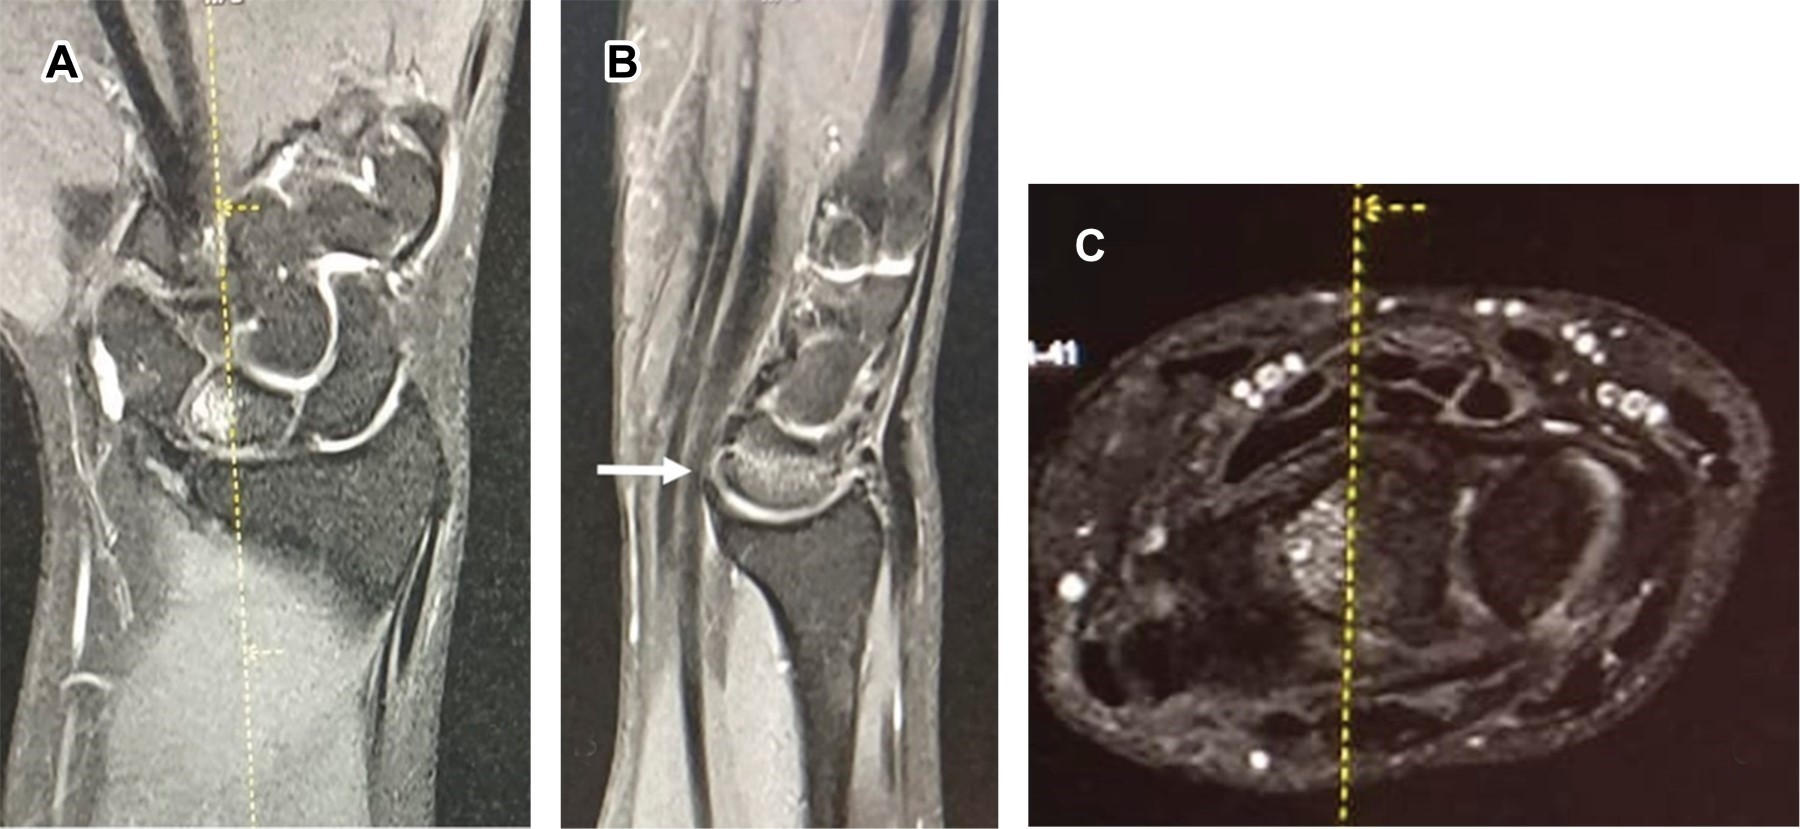

Femenino de 28 años, con dolor de un año en cara dorsal de muñeca, las radiografías simples fueron normales (Figura 1). La resonancia magnética (RM) (Figura 2) mostró incremento de señal en la porción medial del semilunar derecho, correspondiendo a necrosis avascular del semilunar (enfermedad de Kienböck), entidad descrita en 1913, caracterizada por necrosis del hueso semilunar. Generalmente afecta a varones entre los 20 y 40 años, originada por interrupción de la vascularización del hueso semilunar, que inicialmente sufre isquemia y posteriormente necrosis, ocasionando artrosis de muñeca; tiene origen multifactorial, como: factores genéticos, anatómicos, vasculares, traumáticos y ocupacionales. Los pacientes generalmente consultan por dolor de larga evolución, generalmente centrado en el dorso de la muñeca que empeora con la actividad física, puede haber inflamación difusa y dificultad para soportar carga. El diagnóstico clínico debe confirmarse mediante radiografías (que en fases iniciales pueden ser normales) y RM. El tratamiento depende de la etapa de la enfermedad, diferenciando entre estadios aún reversibles o no; en los primeros, las técnicas incluyen injertos vascularizados y las osteotomías de acortamiento para quitar presión al hueso semilunar. En etapas irreversibles, las distintas posibilidades para mejorar la función incluyen las denervaciones, la resección de primera fila del carpo y artrodesis parciales, como último recurso para el control del dolor se reserva la artrodesis total de muñeca.

Figura 2